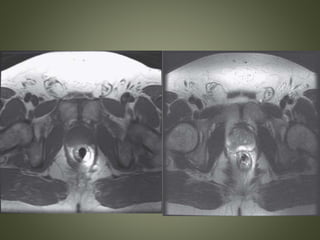

• T2-weighted images - normal peripheral zone

hyperintensity is replaced with low signal

from the dense cellularity of the tumor

 Areas of restricted diffusion appear bright on

DWI sequences and dark on corresponding

ADC maps.

 ADC map is not susceptible to T2 shine-

through artifacts like DWI sequences, therefore

allowing for more sensitive detection

Restricted diffusion in prostate cancer. ADC map

demonstrates restricted diffusion within the peripheral

zone of the right mid-gland